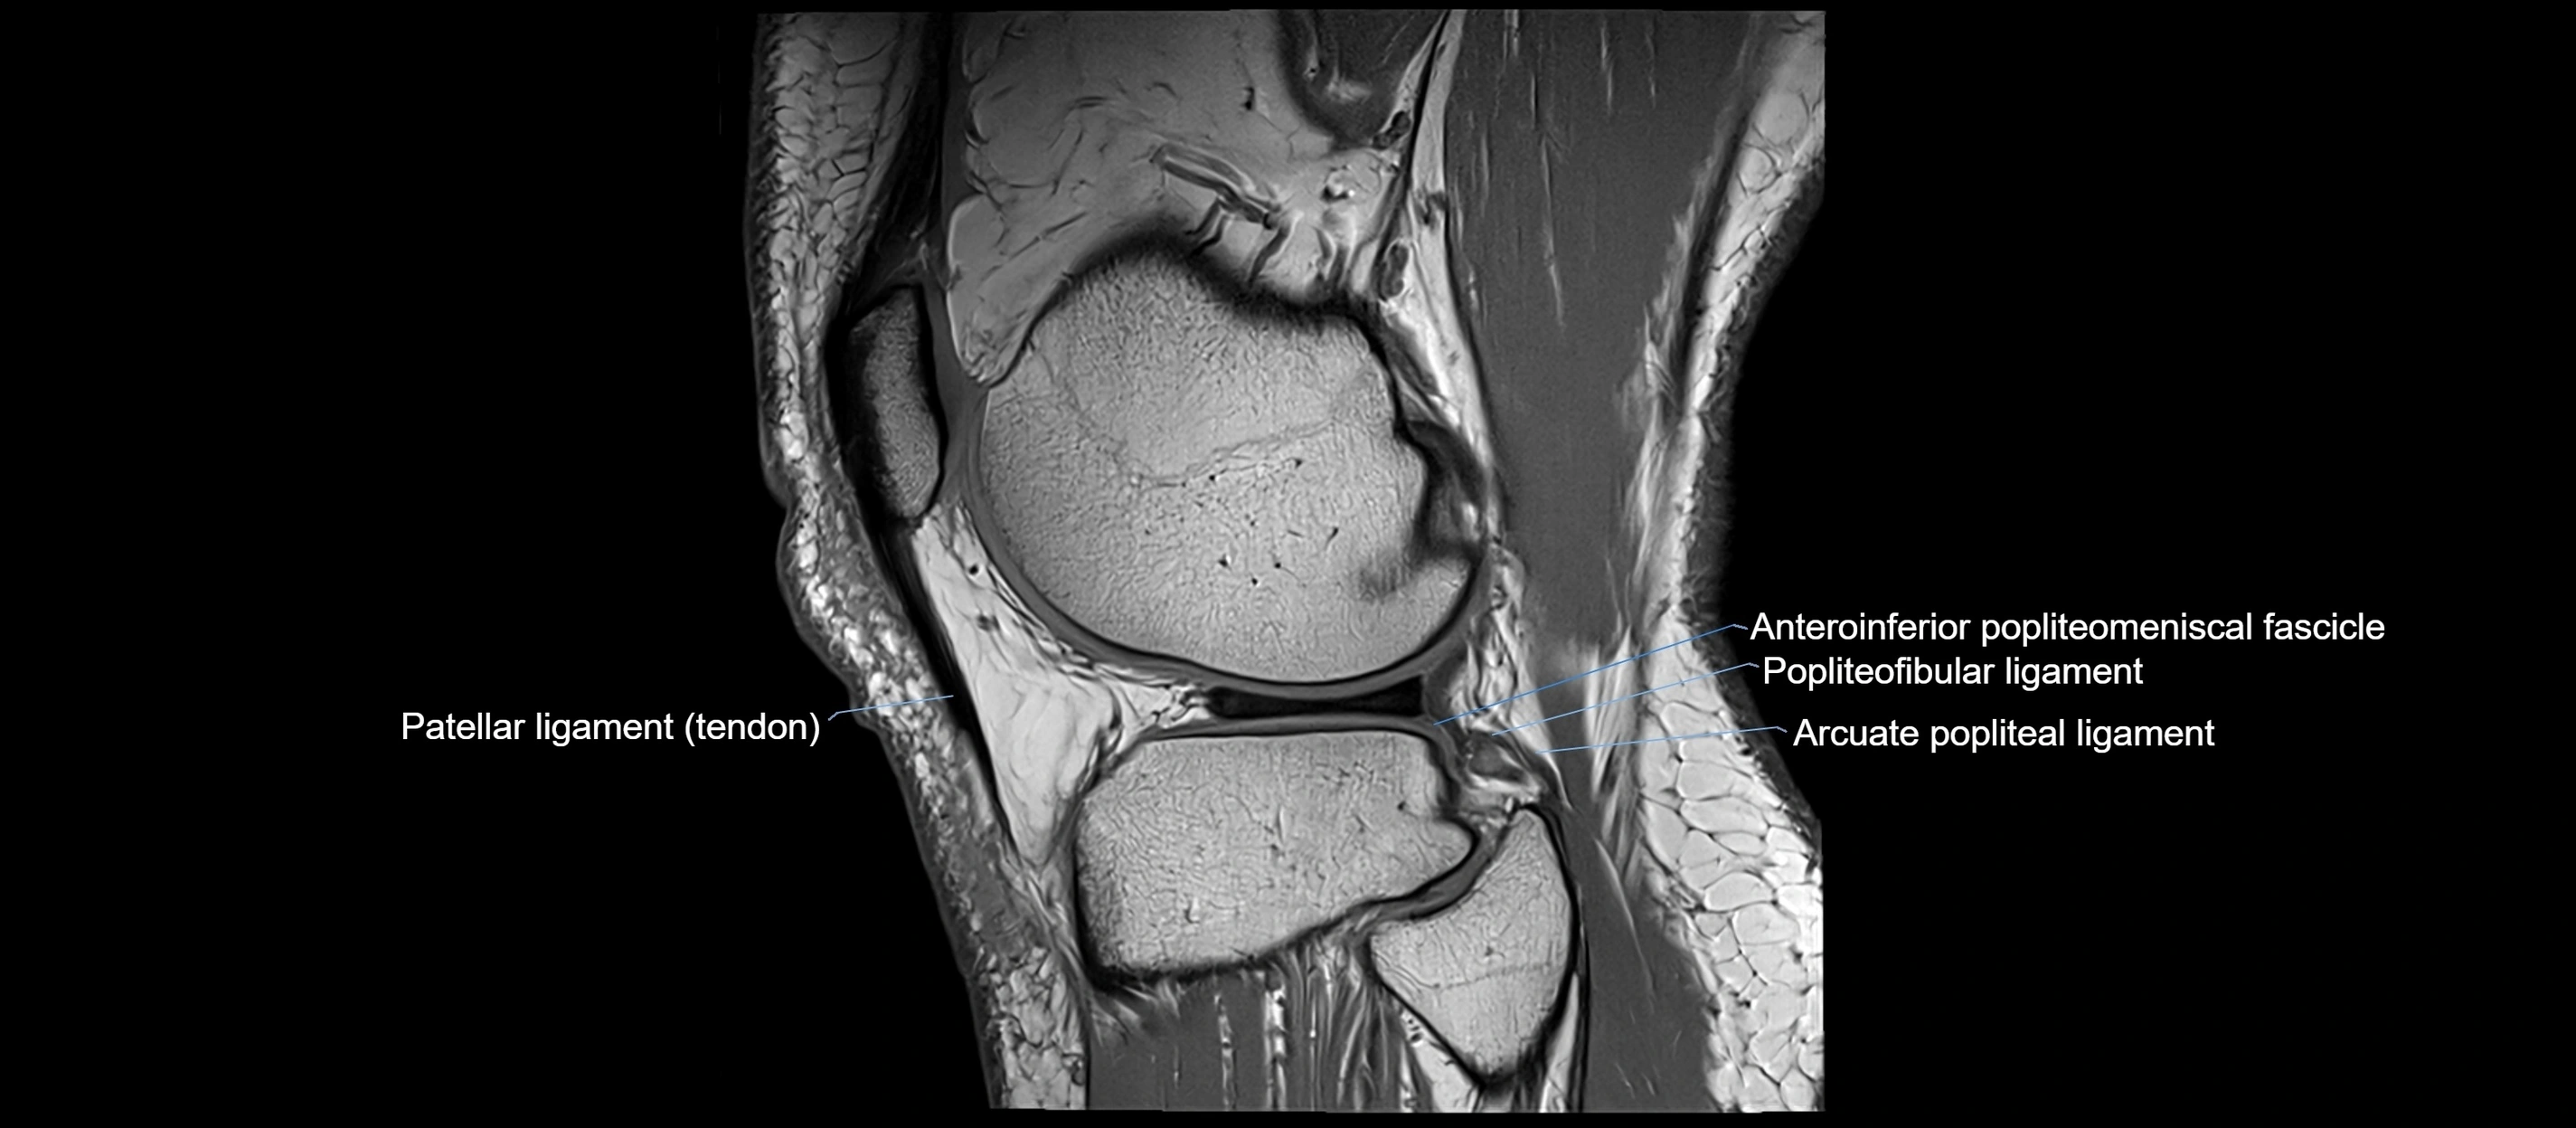

MRI images

image